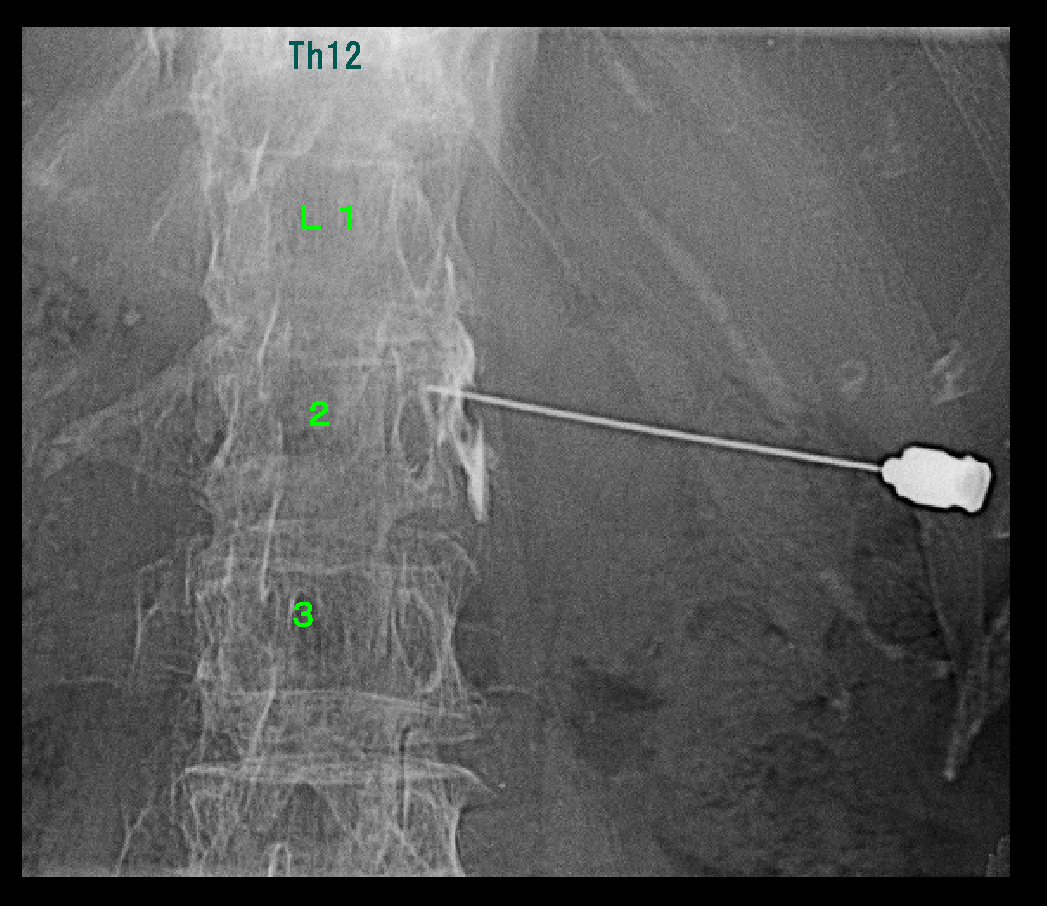

2年後RB.jpg

令和6年10月15日に実施した、Th10神経根ブロックの画像です。

10月24日にはVAS4の背部痛はVAS0となったと報告していただきました。